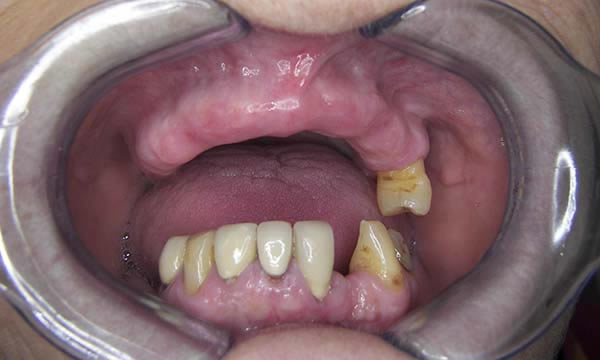

This lady had a very comfortable but loose denture that she had been using for many years. With the loss of her UR5 she decided to close the space and incorporate it into a new implant retained denture. She also decided to replace her lost LL2 with an implant retained crown.

The Kerator overdenture attachment system was used to provide predictable and stable retention for her maxillary denture and the single implant retained crown closed the lower anterior space well. Restoring both form, maxillary lip support, function and confidence.